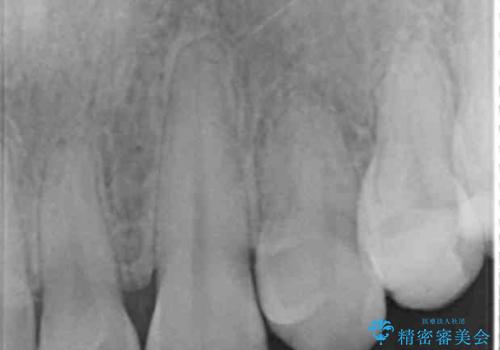

- K-POP(Kポップ)アイドルのような歯にしたいと希望され来院された患者様です。

矯正を途中でやめてしまったとのことで、歯に矯正の接着材が残っており着色も顕著でした。

奥歯の咬合面にはレジンが盛られた状態でした。

見た目と咬み合わせを改善するため、セラミッククラウンによる治療を行いました。

綺麗な仕上がりにご満足下さいました。

奥歯の咬み合わせも良くなったと喜んで頂けました。

クラウンの種類:オールセラミッククラウン スタンダード